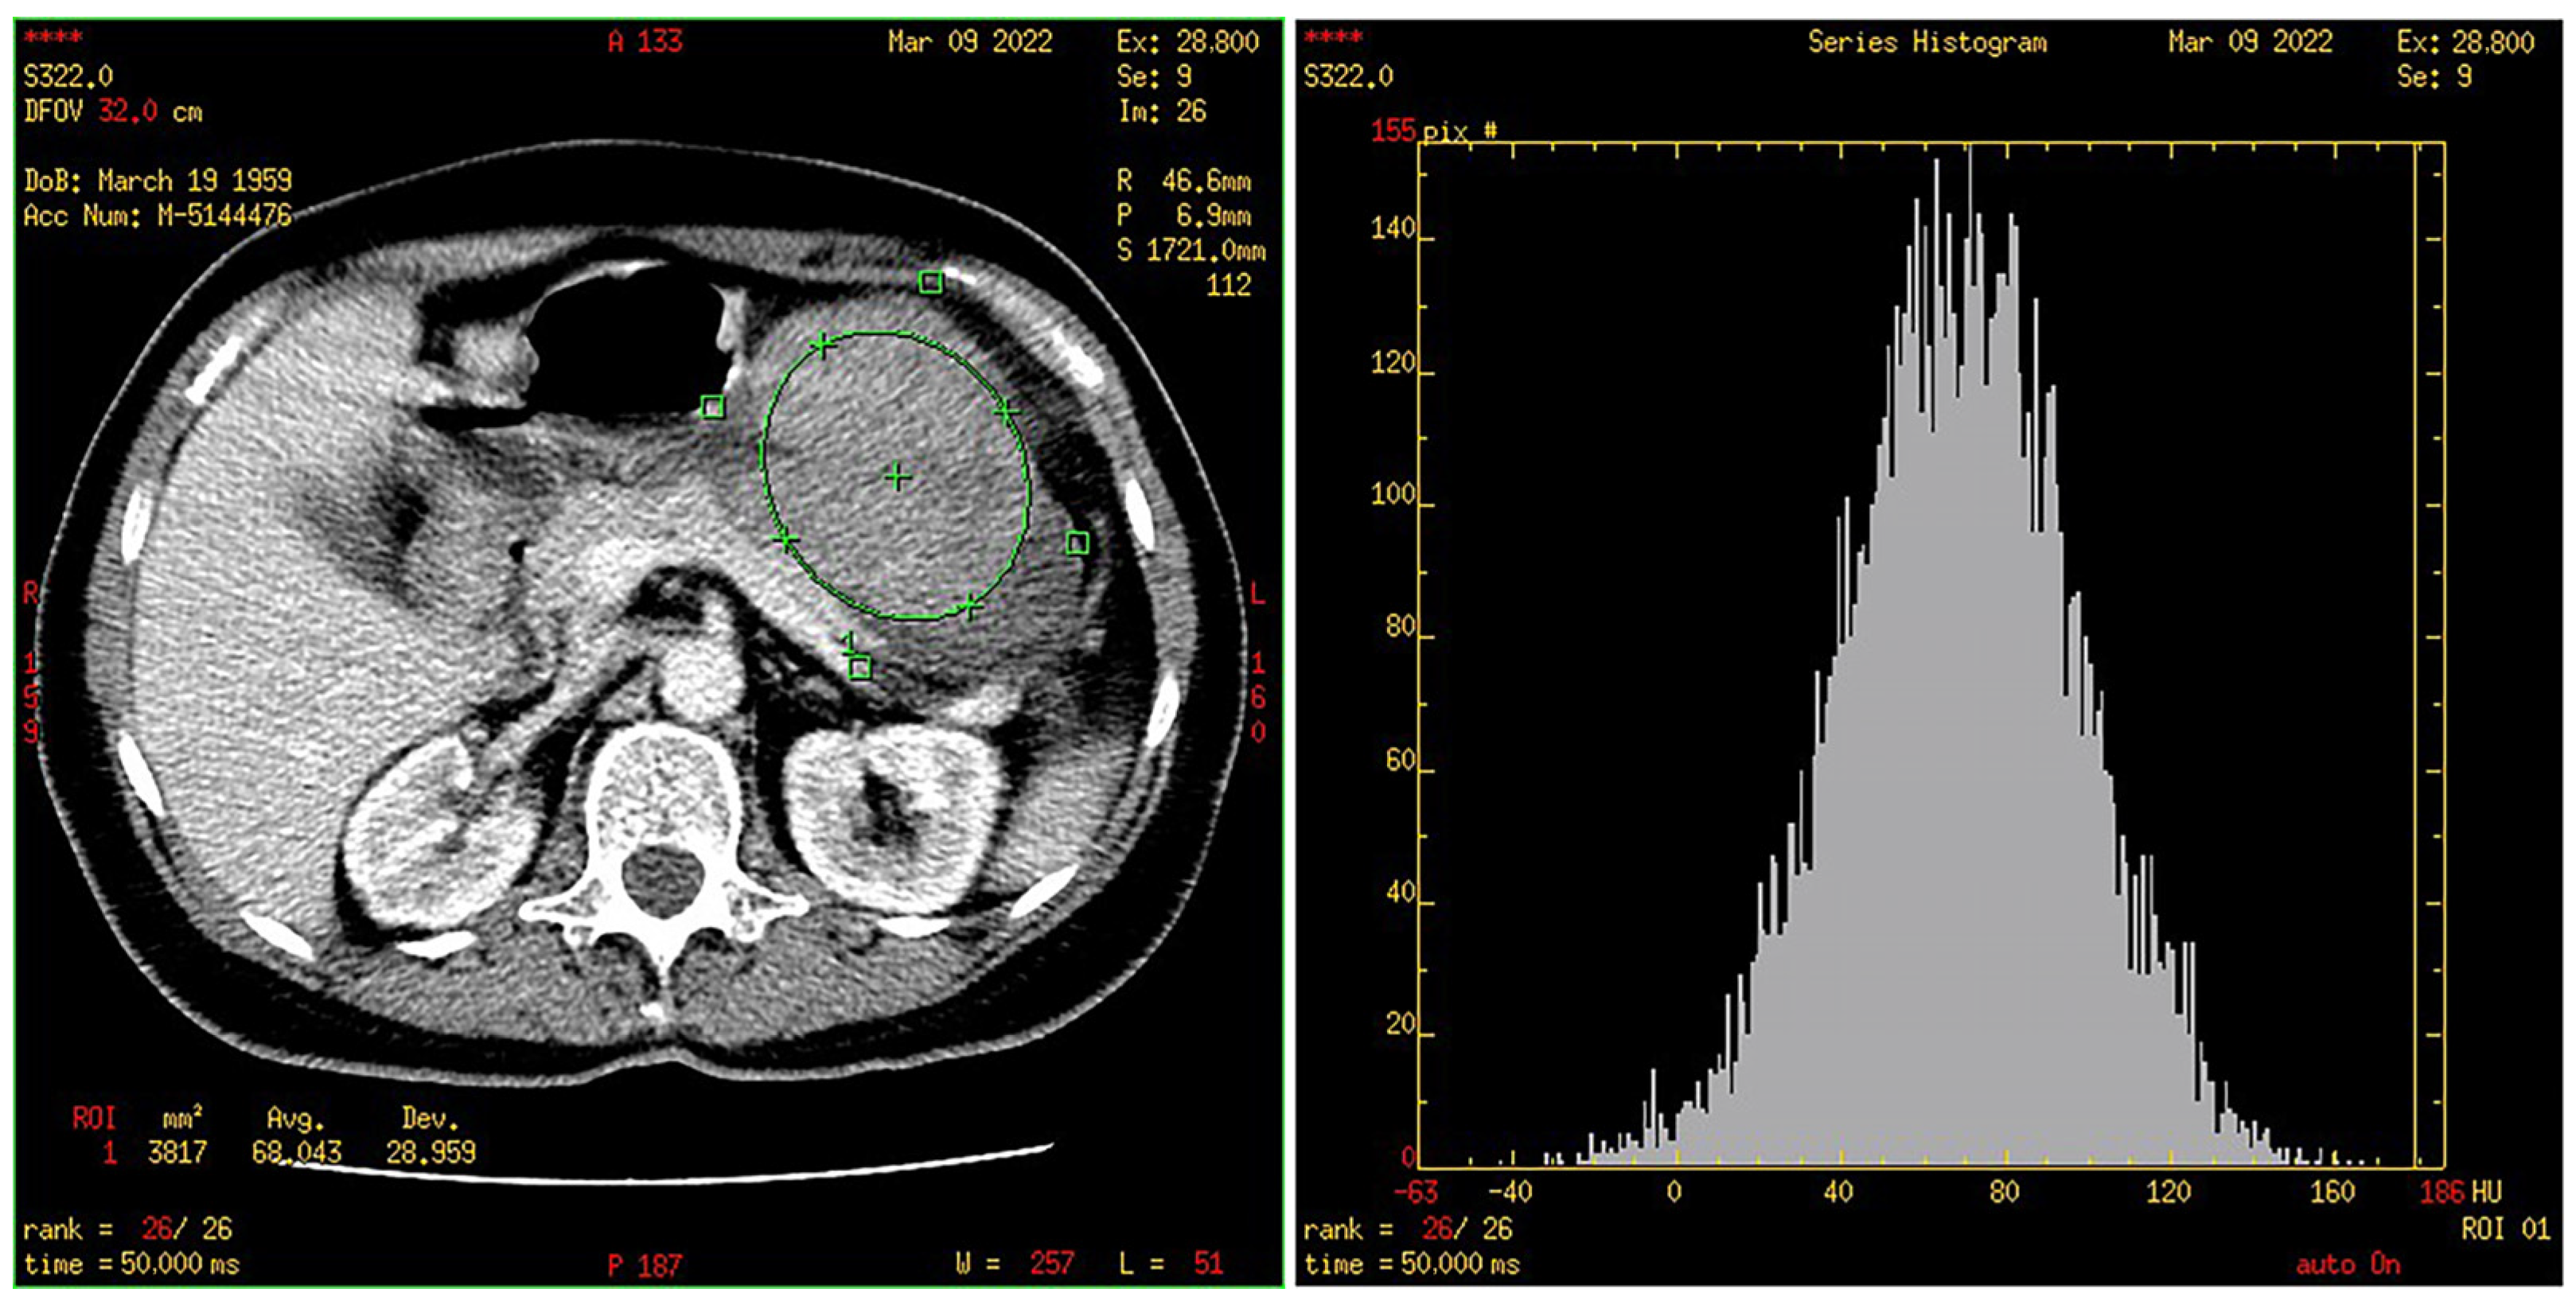

2.4. CT Texture Analysis

3.4. Histogram Parameters in HR and LR Group